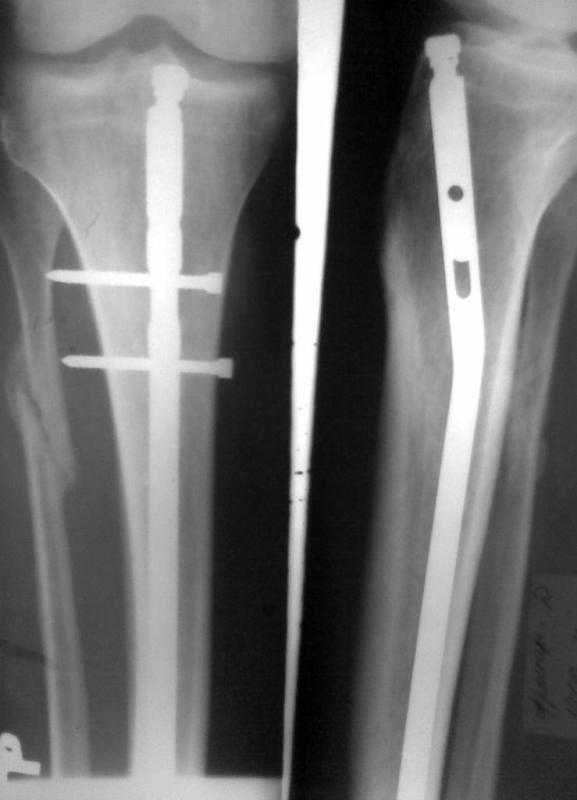

Больному произведено ОМС перелома голени блокирующим стежнем 2 мес. назад. Через 1 мес

больной начал наступать на ногу. В результате такая картина. Удален сломаный конец винта.

Интересует вопрос о дальнейшей тактике лечения. Кто может посоветовать как дальше

поступить. Оставить все как есть и приступать на ногу, провести замену стержня на другой или

поступить как-то иначе. Спасибо за советы и предложения